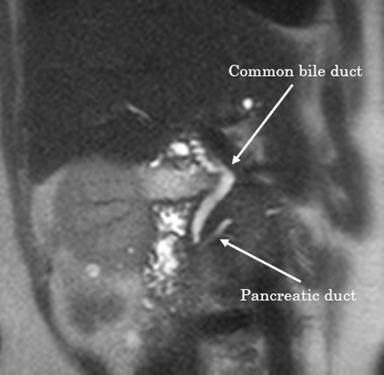

A 60-year-old woman presenting with no symptoms and no history of biliary colic underwent routine abdominal ultrasonography (US) as part of a medical check-up. The US results revealed a nodular protrusion sized 15 mm at the neck of the gallbladder (Figure 1). Despite this abnormality, the patient’s abdomen was unremarkable on physical examination. Neither the results of routine blood tests, which revealed serum carcinoembryonic antigen concentration (CEA) and CA 19-9 levels within normal ranges, nor magnetic resonance cholangiopancreatography (Figure 2), which detected no pancreaticobiliary maljunction, indicated any other abnormality. Although the nodular protrusion seemed likely to be a lymph node, gallbladder cancer could not be ruled out because it was a wide-based protrusion. To determine whether the protrusion was cancerous, laparoscopic cholecystectomy was performed using the standard 4-port technique for diagnosis and treatment. The intraoperative findings indicated that the protrusion was likely not cancerous. The postoperative course was uneventful and the patient discharged on the fourth postoperative day without any complications.

Figure 2. Magnetic resonance cholangiopancreatography revealing absence of pancreaticobiliary maljunction. |